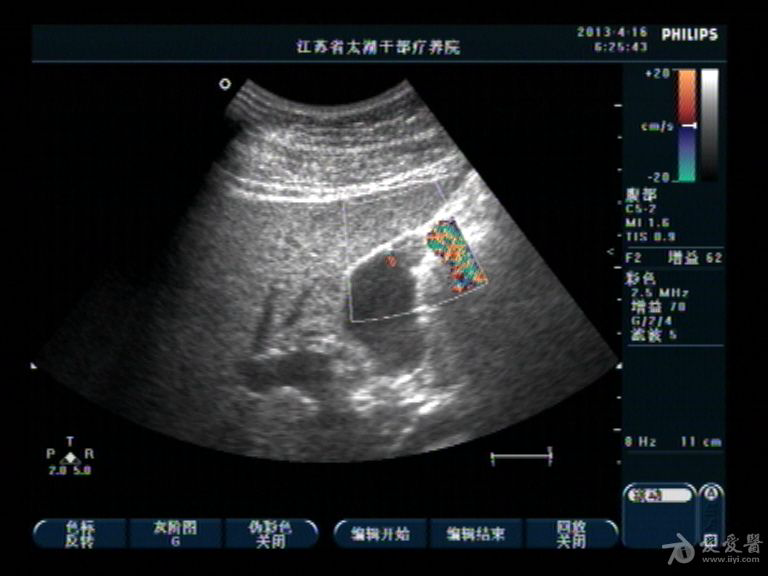

胆囊底部稍低回声区,胆泥沉积?胆囊癌不像吧?,请分析

男性,40,无右上腹痛